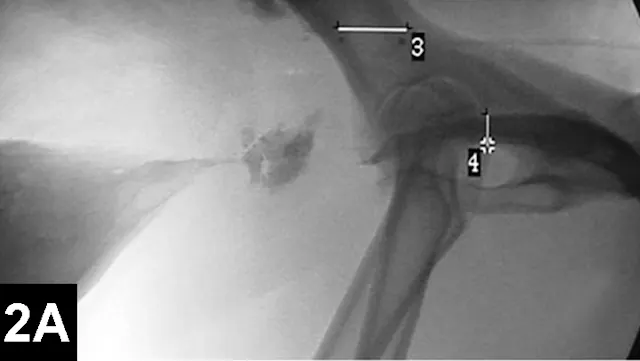

Clinical improvement can be achieved in 75% to 90% of animals treated with self-expanding metallic stents (Figure 1), an IR procedure.4 Immediate adverse events were mostly minor; however, a perioperative mortality rate of about 10% was reported. Longer-term adverse events included shortening of the stent, fracturing of the stent, progressive tracheal collapse, and excessive granulation tissue.

Figure 1A: Serial lateral fluoroscopic images of a dog with tracheal collapse.

A positive pressure ventilation demonstrates maximal dilation of the trachea. A marker catheter in the esophagus is used to account for radiographic magnification.